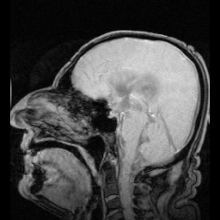

我们 1400~1500ml 的大脑中,具有 125-150ml 的脑脊液。

21.jpeg

虽然脑脊液的总量并不是很多,但大脑每天都会产生 500ml,并重吸收 500ml。

大脑内的脑脊液总是维持在动态平衡的状态,在重吸收的过程中,代谢废物会被转移到血液中去。